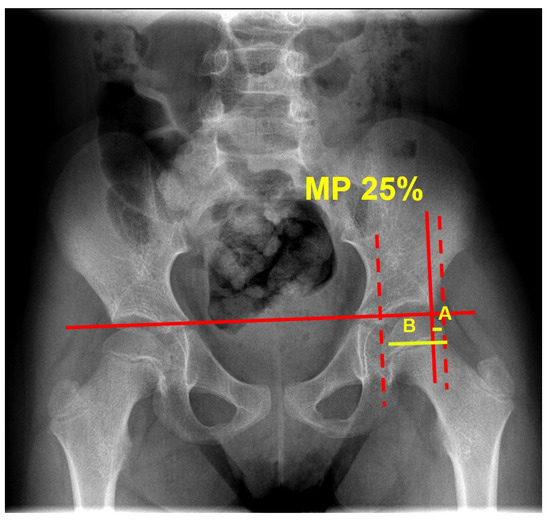

| MP mean value a | 24.8 ± 8.5 (0–39.5) | 24.8 ± 8.2 (0–39.5) | 24.8 ± 8.9 (0–39) | 0.989 |

| MP median value b | 25.0 (19.1–31.4) | 24.2 (20–31.1) | 26.2 (18.9–32.6) | 0.574 |